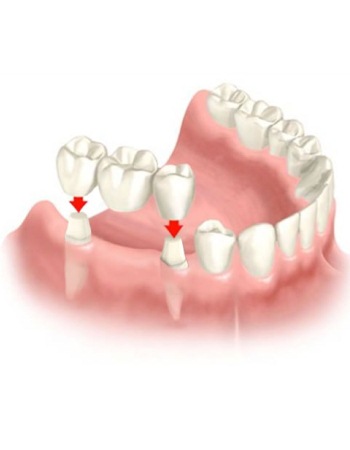

Prótesis dental fija total y parcial

⚡La rehabilitación oral es la especialidad de la odontología encargada de diagnosticar los problemas dentales de un paciente y determinar los tratamientos que se deben llevar a cabo para devolver la estética y funcionalidad.

⭐Para que la rehabilitación oral sea óptima, requiere de modernos procedimientos, tecnología de punta y trabajar de la mano con otras disciplinas de la odontología, como la periodoncia, endodoncia, implantología y ortodoncia👇👇👇